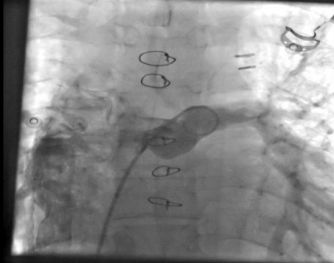

A 30 years old Male with history of complex congenital disease as  Abdominal and atrial situs solitus, , Levocardia , L-looped ventricles, Dominant left sided ventricle with RV morphology with moderate to severe systolic dysfunction(GEF:35%), also Both AV-valves empty to RV(DIRV),Moderate to severe left and right AV valve regurgitation, Both great arteries arise from dominant ventricle(DORV),Aorta was anterior and right sided to PA(D-malposition of great arteries),PA closed surgically with no ante grade flow,  confluent PA branches(RPA=1.4mm,LPA=1.4mm),Left sided aortic arch, Patent Glenn shunt with normal respiratory variation and low velocity laminar flow,Patent conduit between IVC and RPA with slow flow ,4mm fenestration with MPG:4 mmHg, Moderate size secondum type ASD( Fontan surgery, intracardiac tunnel with fenestration).(fig1,2,3)

Fig. 2: CMR showed Patent conduit between IVC and RPA with slow flow, Fontan surgery, intracardiac tunnel with fenestration.

Fig. 3: Angiography AP View showed conduit between IVC and RPA, Fontan surgery, intracardiac tunnel with fenestration.

Figure 2

Figure 3